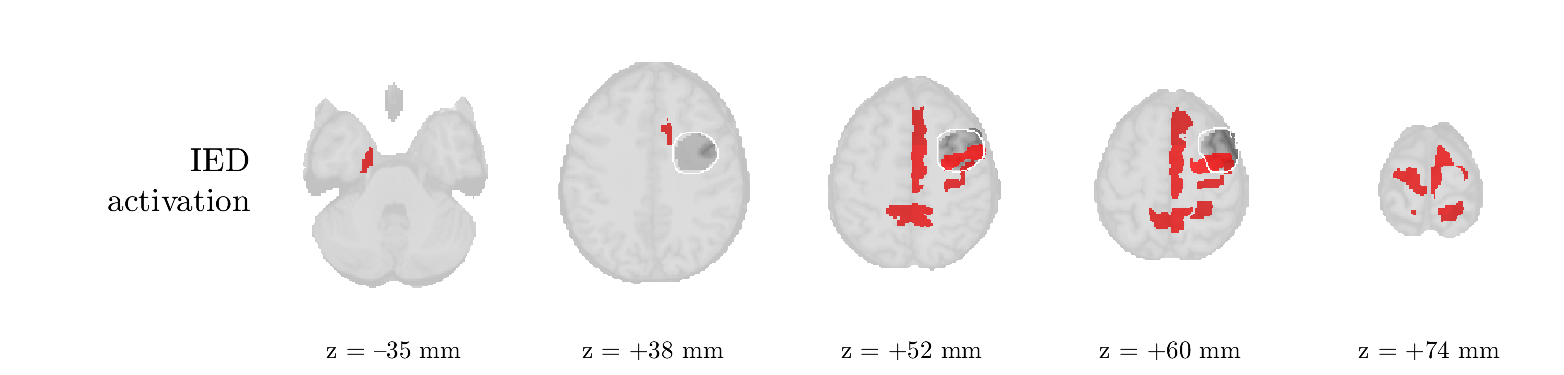

Patient 1

We analyze the solution with sources. Figure 1 shows the EEG signatures and HRF waveforms. One of the sources is highly correlated to the MWF reference (in grey), which was already known from Table B.3. This IED-related source had a typical low-frequency spectrum, which is expected for the typical spike-and-wave interictal discharges. The topography is relatively diffuse, although the highest amplitudes are mostly in the left hemisphere. This is in accordance with the lateralization of ictal onset zone (left temporal lobe, cfr. Table 1). There are some noteworthy observations to be made about some of the other components. The fourth has an unusually sharp spectrum, is mainly localized on two nonadjacent center electrodes, and is sustained for a single period of many seconds Hence, this component likely captured an artifact (of yet unknown origin), although we spotted no large-amplitude changes in the EEG itself. Similarly, the third source is only present at one frontal electrode, and exists in a frequency range above 20 Hz. It might represent a muscle artifact, e.g., due to frowning or twitching of some muscles in the forehead. The HRFs of all ROIs are shown in Figure 1(b). Two of the basis functions seem to have converged to a very similar waveform, which is an unfortunate possibility if two initial HRFs are too close to the same local optimum in their respective parameters. This reduces the expressive power of the basis set, which is clearly visible, since many ROIs have a nearly identical HRF. One of the twenty ROIs with the highest-entropy HRF overlapped the IOZ, although clearly this HRF (bold line) is not among the most dissimilar waveforms for this patient. This is also visible in Figure 2: both the HRF entropy and extremity maps show a small overlap with the delineated IOZ. Despite the good correspondence in the EEG domain, no significant (de)activation of the IED-component is found inside the IOZ.